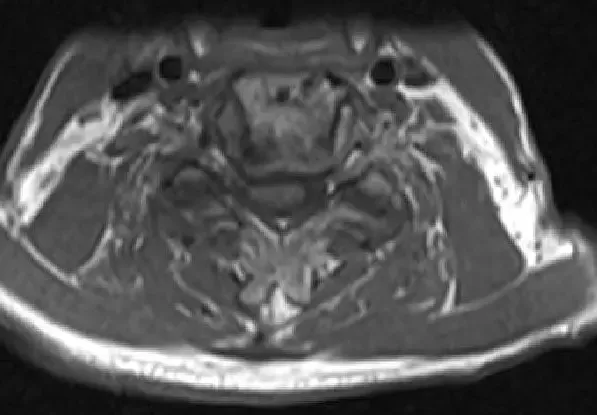

Imagen de resonancia magnética T2 Corte axial que muestra estenosis y compresión severa de la médula espinal en C3-4